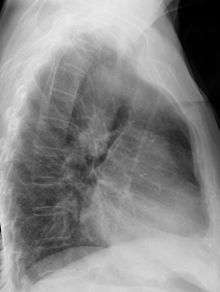

During pregnancy, prenatal ultrasound may reveal the abnormal course of the arch. On chest radiography, a right-sided aortic arch is visualized by the aortic knob (the prominent shadow of the aortic arch) that is located right from the sternum instead of left. Complex lesions are often assessed by MRI or CT.